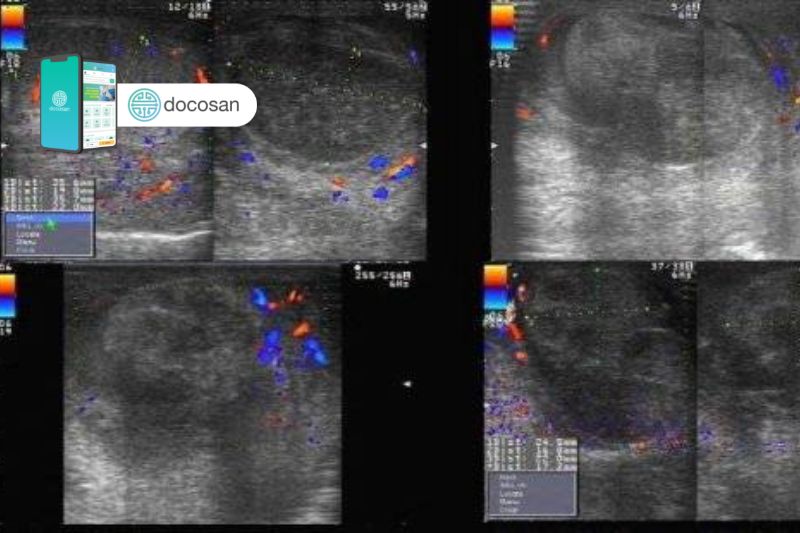

- Siêu âm Doppler tinh hoàn là một kỹ thuật thực hiện đơn giản, dễ dàng và hoàn toàn nên dường như là cận lâm sàng hình ảnh học luôn được chỉ định để hỗ trợ phát hiện chẩn đoán sớm bệnh xoắn tinh hoàn do siêu âm phổ doppler sẽ thấy dòng máu tới tinh hoàn giảm tưới máu hoặc không thấy tín hiệu mạch.

- Ở trẻ nhỏ thì hình ảnh xoắn tinh hoàn trên siêu âm Doppler sẽ không điển hình như người nam giới trưởng thành, do đó cần kết hợp các thông tin thu thập được trên lâm sàng của trẻ để đưa ra được chẩn đoán chính xác nhất giúp tiên lượng và điều trị sớm cho người bệnh.